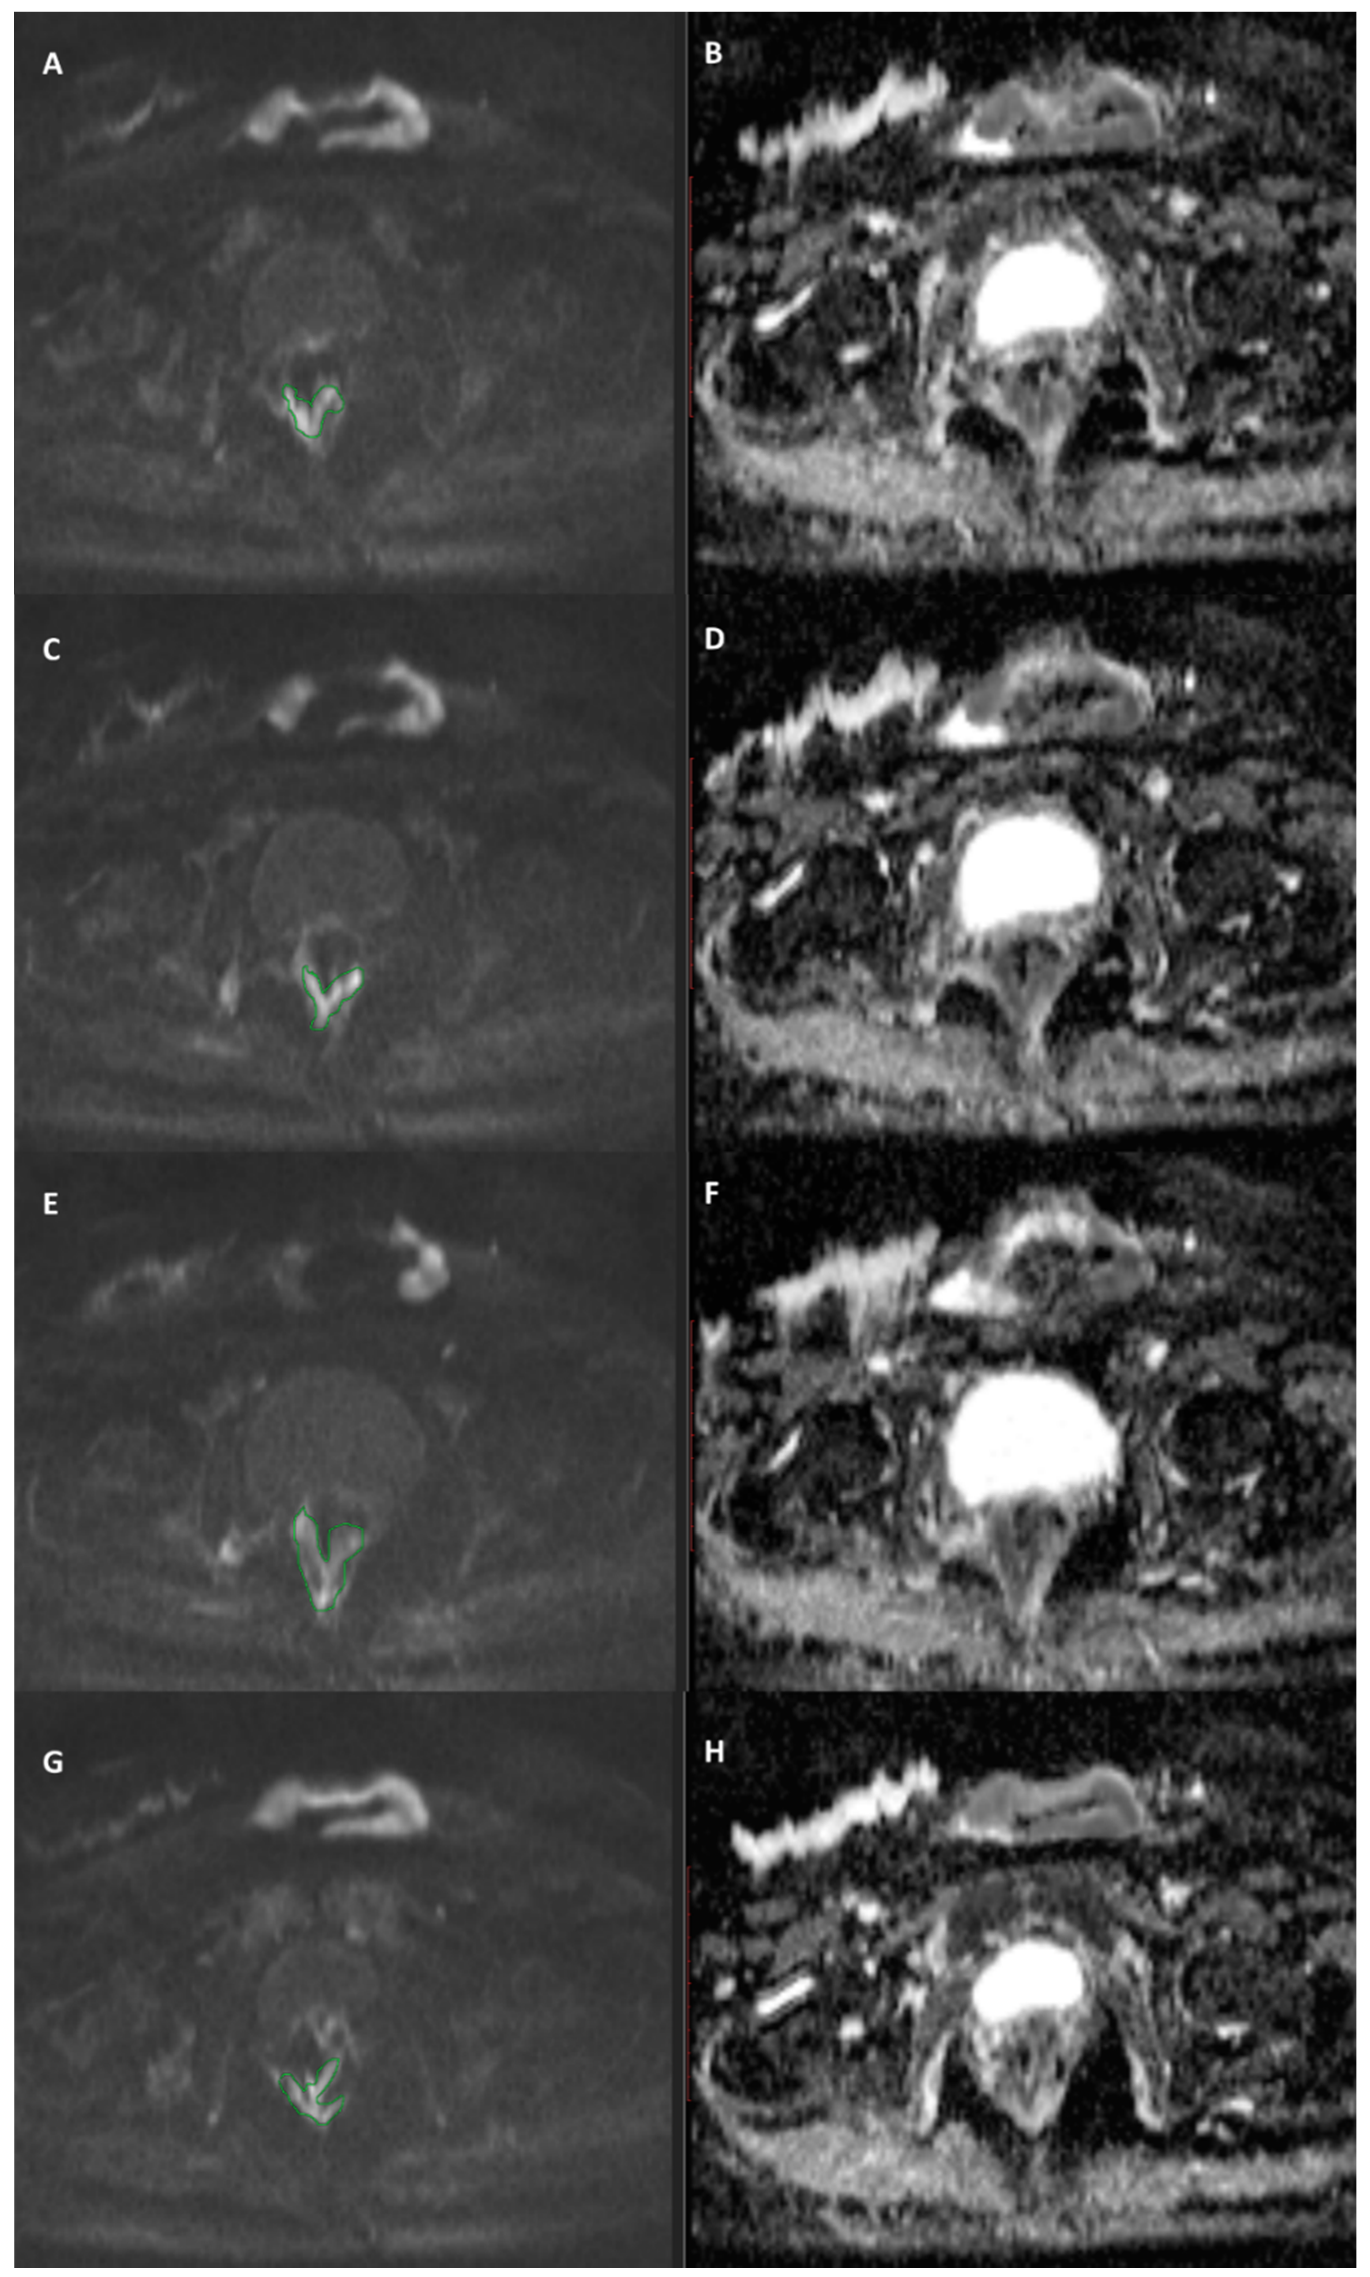

DWI Features